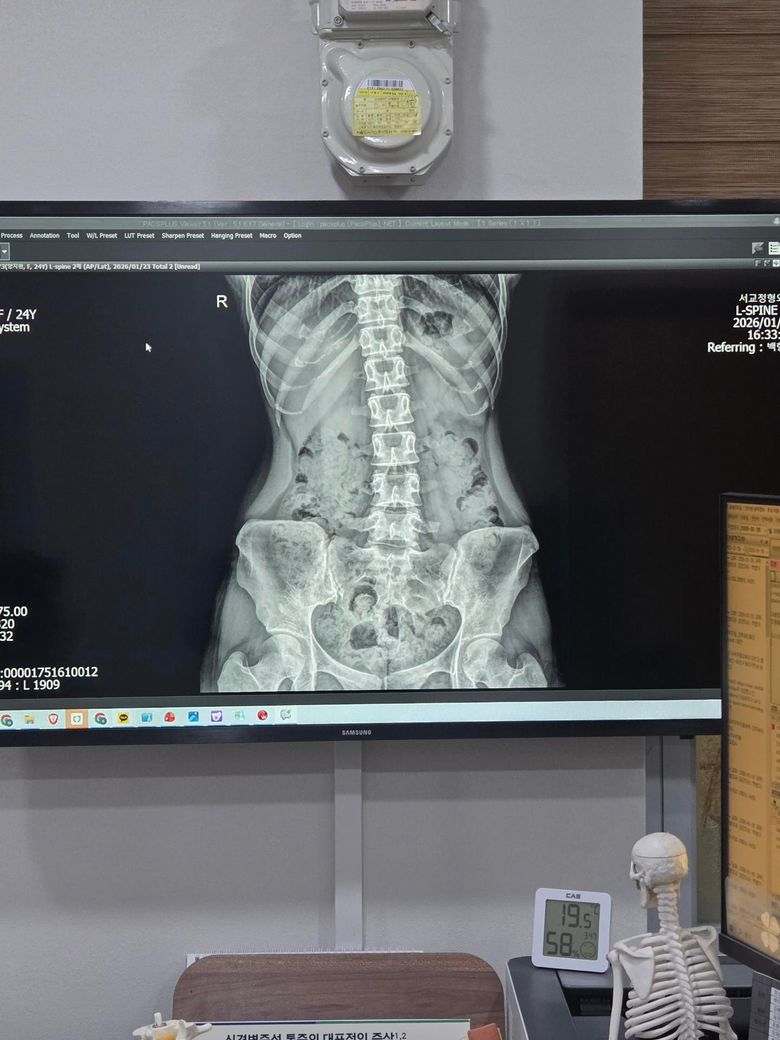

x-ray 상으로 보아서는 일자 허리와 골반의 틀어짐, 척추측만증도 있어 보입니다.

또한 현재 엑스레이상 허리의 만곡이 부족하며 체형이 약간의 한쪽으로 기울어진것으로 보여집니다.